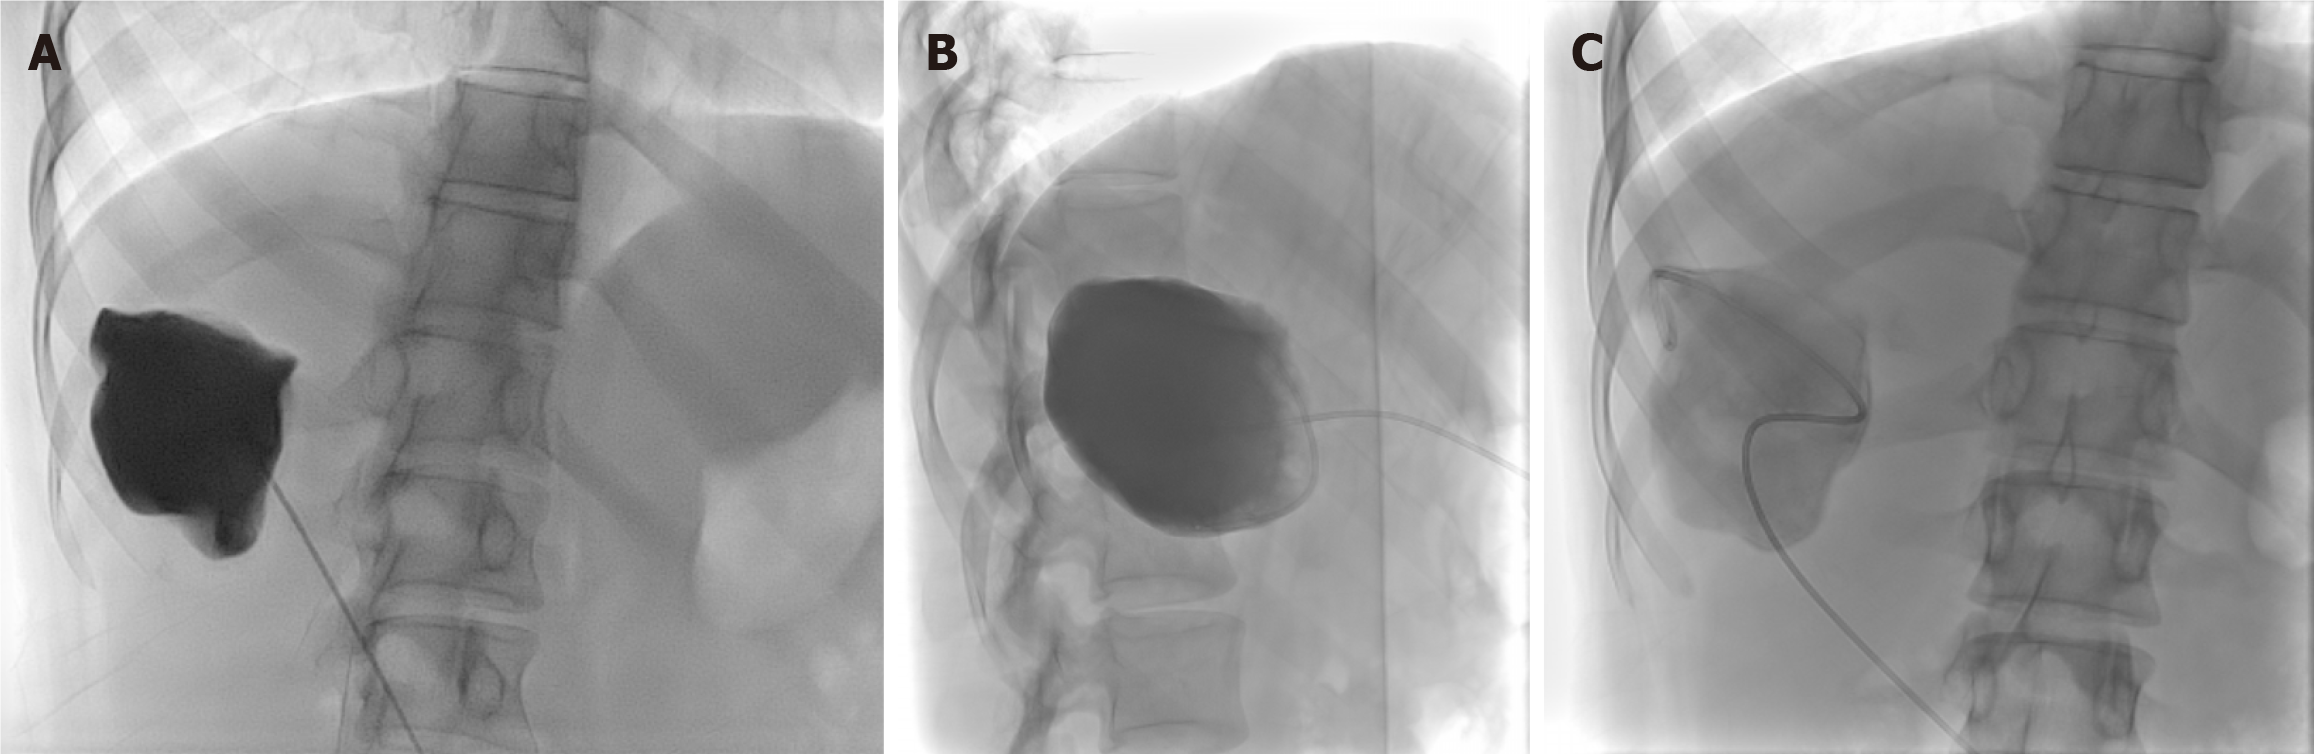

Figure 5

Figure 5 Puncture-aspiration-injection-reaspiration procedure. A-C: Ultrasound (A) and axial computed tomography image (B) depict a cystic echinococcus 1 hydatid cyst in the right lobe of the liver. Fluoroscopic spot image (C) shows opacification of the cyst cavity following contrast injection, confirming correct intracystic placement with no evidence of cysto-biliary communication; D-F: Axial ultrasound (D) and coronal T2-weighted magnetic resonance imaging image (E) in a different patient depicts a cystic echinococcus 3a hydatid cyst in the left lobe of the liver. Fluoroscopic spot image (F) obtained during the puncture-aspiration-injection-reaspiration procedure shows opacification of the cyst cavity, with the floating membranes visualized as curvilinear filling defects, with no evidence of cysto-biliary communication.

Figure 6 Puncture-aspiration-injection-reaspiration procedure. A-C: Frontal fluoroscopic spot image (A) demonstrates intracystic injection of contrast, with no evidence of cysto-biliary communication. Lateral fluoroscopic spot image (B) after aspiration of the previously injected contrast from the hydatid cyst. Frontal fluoroscopic spot image (C) after instillation of scolicidal agent into the cyst cavity.

The procedure is performed under US with fluoroscopy or CT guidance. The first step is puncture (P), where the cyst is punctured (usually with an 18-G needle) through a thick cuff of normal liver parenchyma, to reduce the chances of fluid leakage and bleeding. Initially, 20% of the cyst fluid is aspirated (A), and then contrast is injected (10% of the cyst fluid, or half of the initially aspirated volume) under fluoroscopy or CT guidance to look for cysto-biliary communication. The aspirated fluid is also examined for physical appearance, bilirubin (bilirubin dipstick test), and scolex viability test (motility and dye tests). If there is cysto-biliary communication (yellow coloured cyst fluid, or positive bilirubin dipstick test, or opacification of biliary radicles on contrast injection), then PAIR may be terminated or can be converted into S-CAT[24]. In the absence of cystobiliary communication, rapid cyst aspiration decompresses the cyst and allows for detachment of the parasitic layers from the cyst wall.

If there is no evidence to suggest cysto-biliary communication, then the next step is injection (I) of the scolicidal agent. The commonly used agents are 95% ethanol and hypertonic saline (20%). Other scolicidal agents include cetrimide (0.1%) and povidone-iodine (10%). It is injected into the cavity and remains within the cyst for 20 minutes. The amount of scolicidal agent injected is 35%-50% of the cyst’s initial volume. Then reaspiration (R) of all the fluid in the cyst is done. Before needle removal, a small amount of normal saline is injected and re-aspirated, and scolex viability tests are repeated. Viable and non-viable scoleces can be differentiated by observing their motility under the microscope and observing the staining pattern with 0.1% eosin or 0.1% methylene blue stain. Live scolices reduce these dyes and lose colour, while dead scolices adsorb and fail to reduce the vital dyes and take up the dye colour[31,32]. If re-aspirated fluid shows viable scolices, then PAIR should be repeated either immediately or within 48 hours[2].